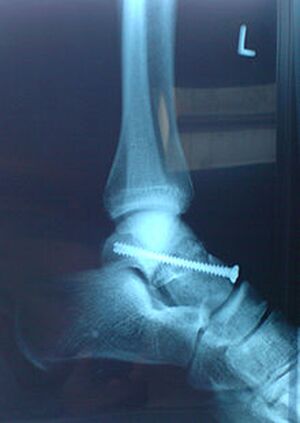

mit einer Schraube "repariertes" Sprunggelenk - Christian Kazur commons.wikimedia.org, CC BY 3.0

Bei Außenbandrissen im Bereich des Sprunggelenkes wird immer öfter ohne Operation behandelt. Nach Verschwinden der Schwellung erhält der Betroffene eine Plastikschiene, mit welcher der Fuß im Sportschuh nahezu wieder normal belastet werden kann. Bis zur völligen Ausheilung vergehen einige Wochen. Der Heilungsprozess kann durch Bewegungs- und Dehnübungen, sowie durch gezielte Elektrotherapie wesentlich unterstützt werden.

Bei Komplettabrissen und in speziellen Fällen ist meist eine Operation notwendig.